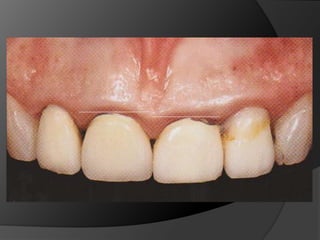

PRINCIPIOS ESTÉTICOSRestauraciones con forma, contorno y color adecuados

PRINCIPIOS ESTÉTICOSRestauraciones conforma, contorno y color adecuados